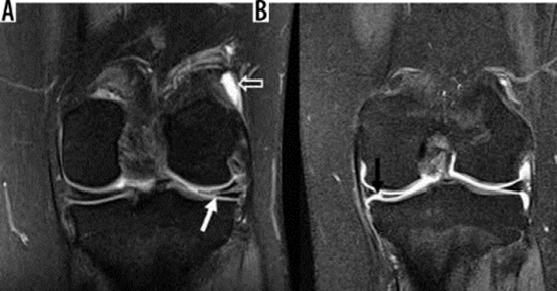

Hình 7. Vết rách ngang sụn. Hình ảnh pd coronal xóa mỡ với tín hiệu tuyến tính trong sụn (mũi tên đóng) kéo dài đến mặt dưới của thân sụn bên, phù hợp với vết rách. Tín hiệu cao (mũi tên mở) ở mặt ngoài, mặt sụn giữa không kéo dài đến bề mặt tạo hình sụn và phù hợp với thoái hóa niêm mạc.

Hình 8. Nước mắt tay cầm xô lệch. A và B là hình ảnh cộng hưởng từ pd xóa mỡ với vết rách tay cầm cho thấy một mảnh sụn dịch chuyển liền kề với dây chằng chéo sau (mũi tên trắng), được gọi là dấu hiệu "dây chằng chéo sau đôi ", cũng như một mảnh sụn bị dịch chuyển trong rãnh liên chất (mũi tên đen). C là hình ảnh pd xóa mỡ với vết rách ở tay cầm cho thấy mảnh bị dịch chuyển ra phía trước (mũi tên trắng), tiếp giáp với sừng trước, được gọi là dấu hiệu "sừng trước kép".